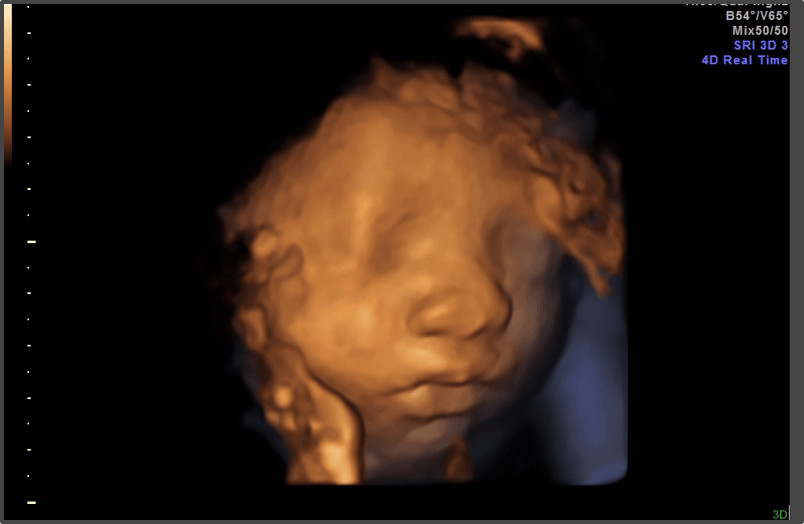

Pregnancy Calculator - Week 28

Your baby is the size of a large eggplant.

Approx Baby Weight: 1.0kg

Approx Baby Size: 37.6 cm

Baby Development

The baby is practicing breathing by inhaling and exhaling amniotic fluid.